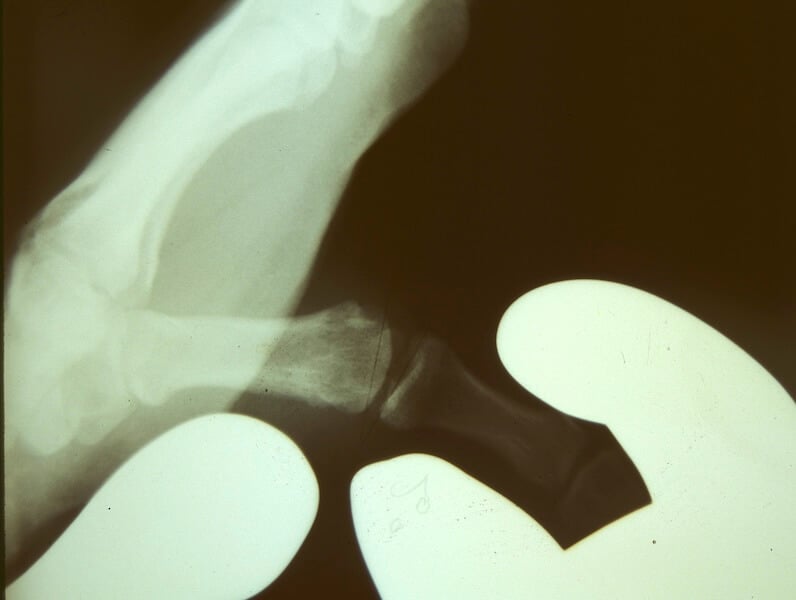

entorse pouce ligament

Radiographie d'une laxité modérée en valgus de la MP du pouce